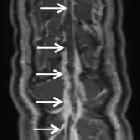

MRI

The clot acutely is isodense on T1 and hypointense on T2 (this can mimic a flow void), with subacute clot becoming hyperintense on T1. All the findings listed in the CT section are also seen on MRI. MRV will demonstrate lack of flow.